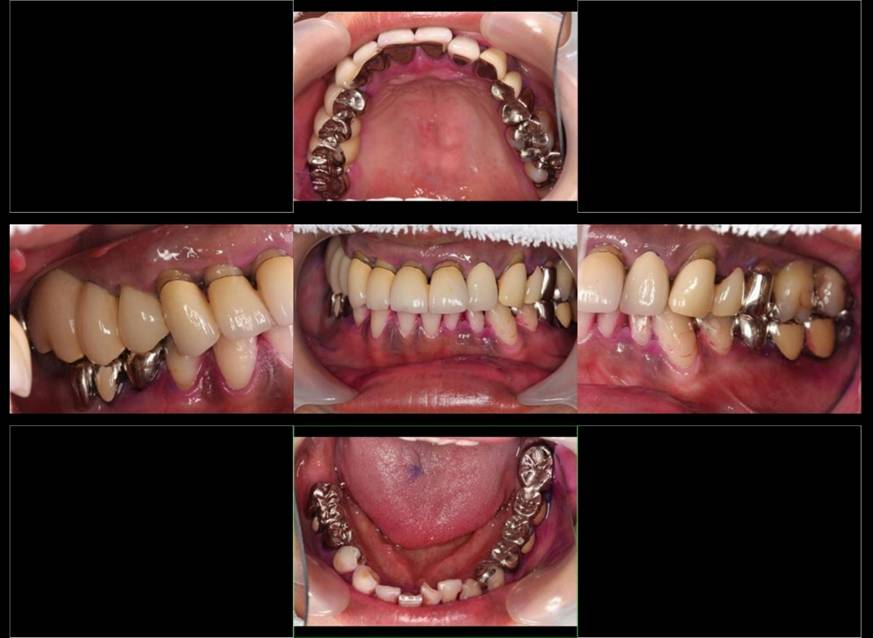

術前。すべての歯が歯周病の末期状態でブリッジ全体がうごいて噛めないとの訴え。右上の犬歯が腫れていました

固定式のブリッジが入っていましたが歯周病で動いています

下顎前歯部には歯石の沈着がみられます

術後。上部構造はハイブリッドレジンです。しっかり嚙めるようになり喜んでいただきました。

上部構造装着後6年。ハイブリッドレジンを使用したため、少し艶がなくなってきました。上部構造の材料には金属、ハイブリッドレジン、セラミックなどがあります。セラミックはきれいですが欠けやすいため、最近はフルジルコニアを使っています。

上顎 少しすり減ってきました。

下顎。12か月に一度メインテナンスをしています。

インプラント装着後6年。順調に経過しています。12か月毎のメインテナンスをしています。